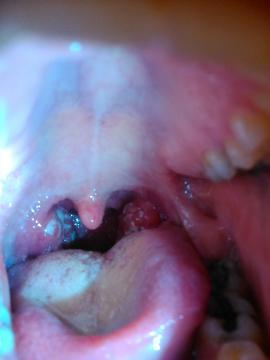

Pro větší náhled klikněte na obrázek

Dobrý deň, 15.8. mi na pohotovosti diagnostikovali anginu a zapal močového mechúra. Nasadili antibiotiká Ciphon 500. Po týždni mi bolo po nich zle tak mi ich zmenili na dalšie - názov ale už neviem niečo dan.... . Pred dvomi dnami som ich dobrala. Celú túto dobu ma bolí hrdlo relatívne málo. V nedelu ma začalo bolieť oveľa viac. Bola som u lekara a povedal že mám tam hnis ale mám ešte počkať. Išla som tam včera to je dva dni potom že to mám stále horšie - nedá sa mi už ani prehltat.. On to však videl tak, že to mám lepšie ako v pondelok. Na čo som začala naliehať, že budú sviatky plus sobota nedela a utorok neordinuje.. takže nechcem behať po pohotovosti.. na to mi dal antibiotiká dalšie.. a po dohode ich mám brat v prípade, že dostanem teplotu( tu nemám asi 6dní).. zajtra to búdu dva týždne a nikto ani len výter ani krv nezobrali nič.. Som z toho na nervi.. v hrdle mám také biele flaky, ktoré stále bolia. Vedeli by ste mi poradiť čo s tým a ci to je následok anginy?? Tie nové antibiotiká nechcem brať, lebo mám pociť že len tipuje pán doktor.. toto by boli už tretie antibiotiká bez dôkladneho vyšetrenia.. Teraz je mi až zle ked si predstavým, že musím čakat do stredy.. Za prípadnu odpoved dakujem.prikladám fotku